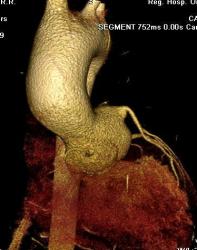

Мужчина 35 лет с клиникой стеноза аортального клапана. На КТ выявлен двустворчатый клапан с обызвествлениями в створках. Луковица аорты и восходящий отдел значительно расширены. Отмечается также вариант отхождения левой коронарной артерии - левая передняя нисходящая и огибающая отходят непосредственно от аорты. Правая коронарная артерия гипопластична.